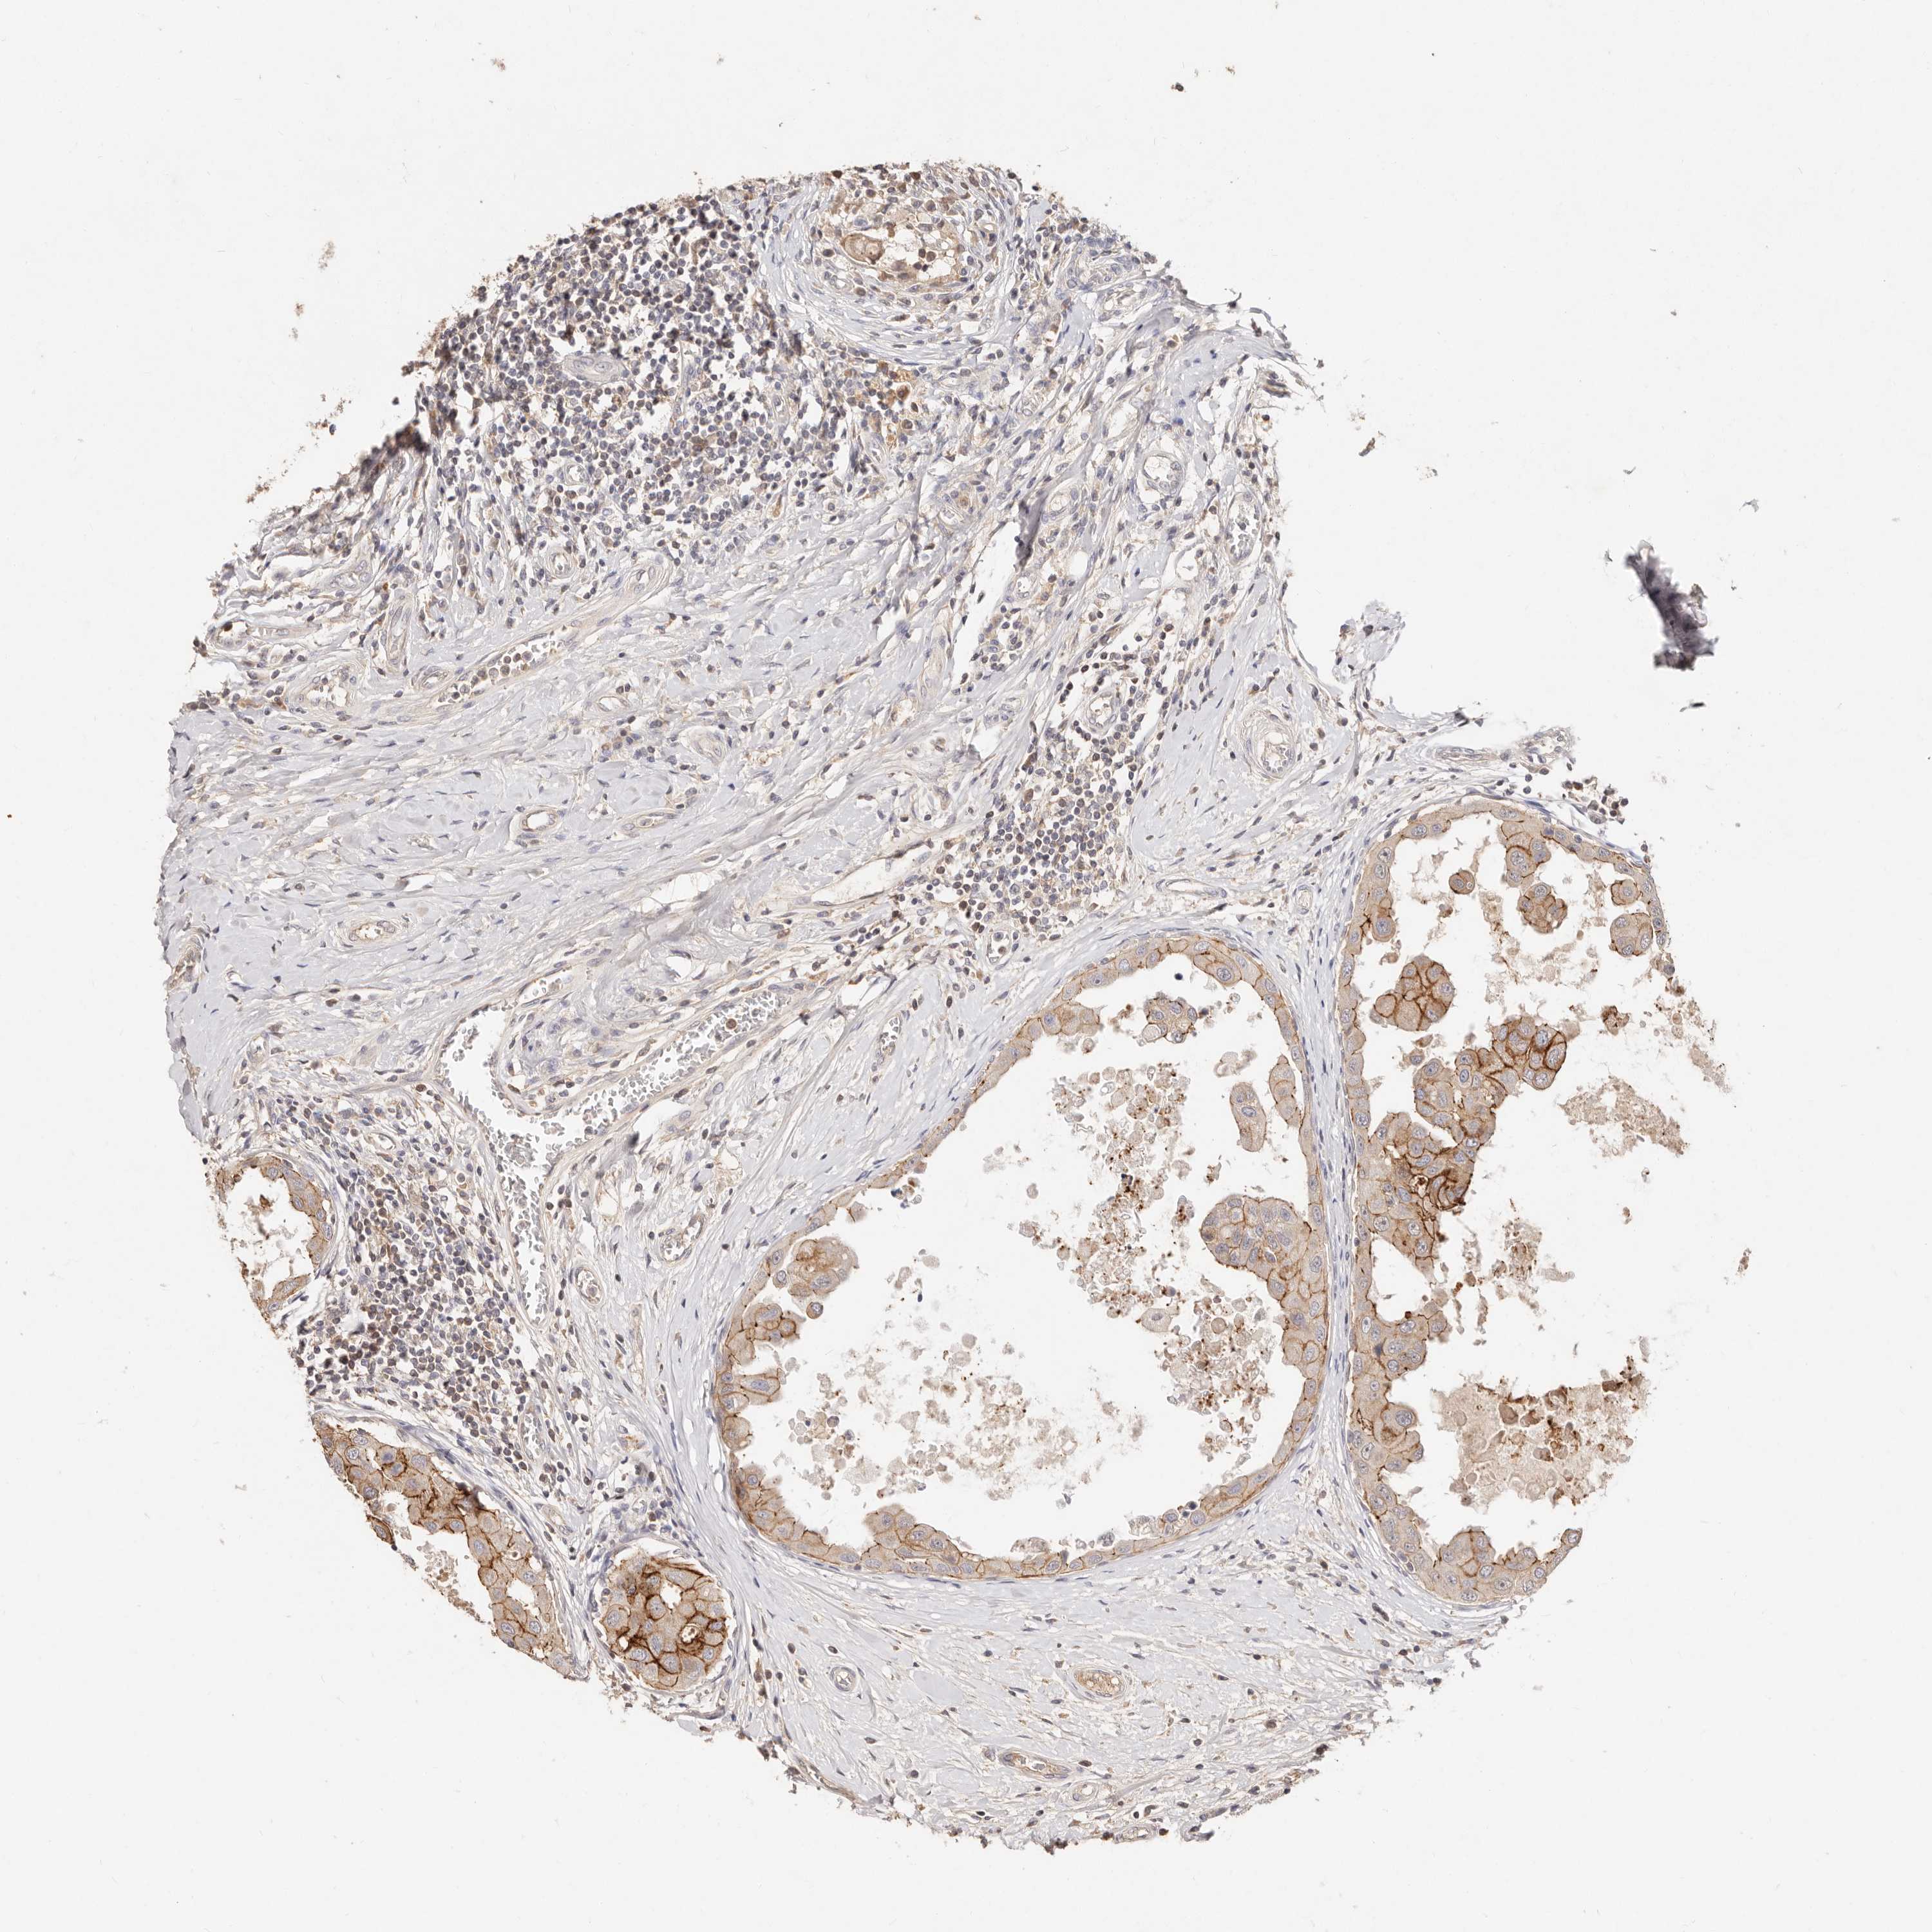

CANCER BREAST CANCER Show tissue menu

BRCA TCGA BRCA VALIDATION PROTEIN EXPRESSION